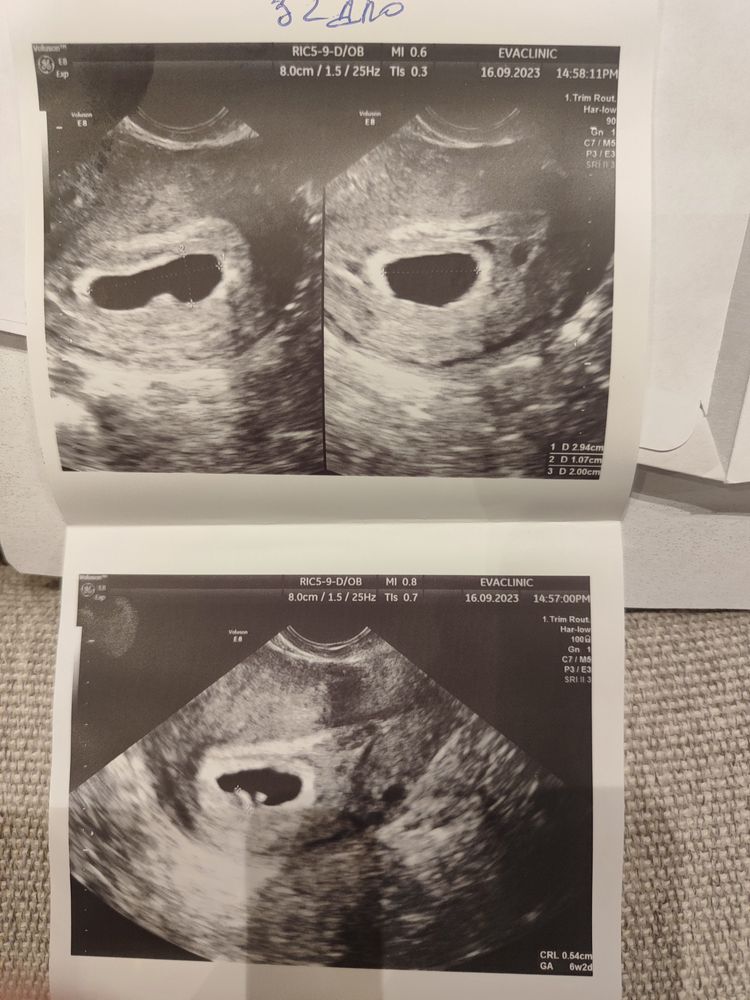

Была на УЗИ:

32 дпо( 6.2 нед) эмбриона нет, жм 3.2. (но врач сомневалась) ПЯ 20.0 неправольной формы (ХГЧ за день до 24тыс.) - ставит замершую, отправляет на чистку

Прикрепляю УЗИ 32 дпо и 34 дпо-... Может кто-то что-то поймет.

УЗИ где виден желт.мошок и какой-то бугорок который растет